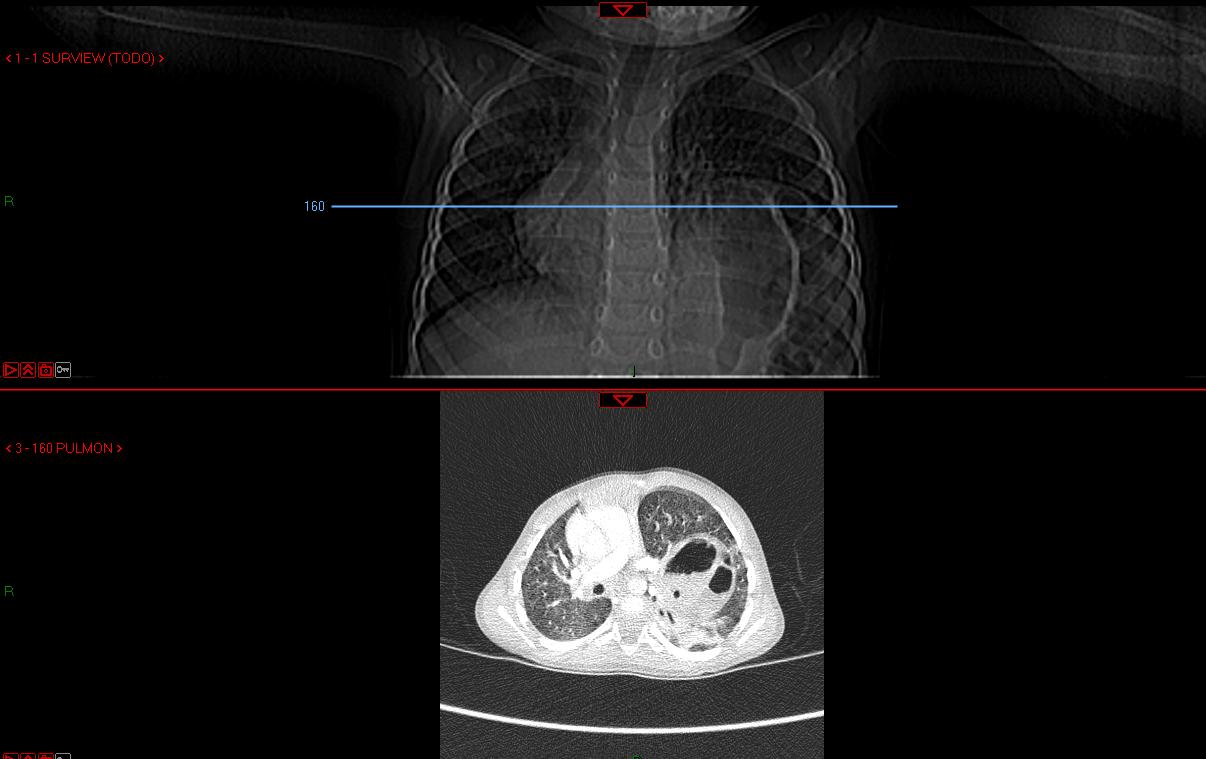

El especialista, tras escuchar los comentarios acerca de la situación clínica y el motivo de ingreso, le indica la necesidad de realizar una tomografía computerizada.